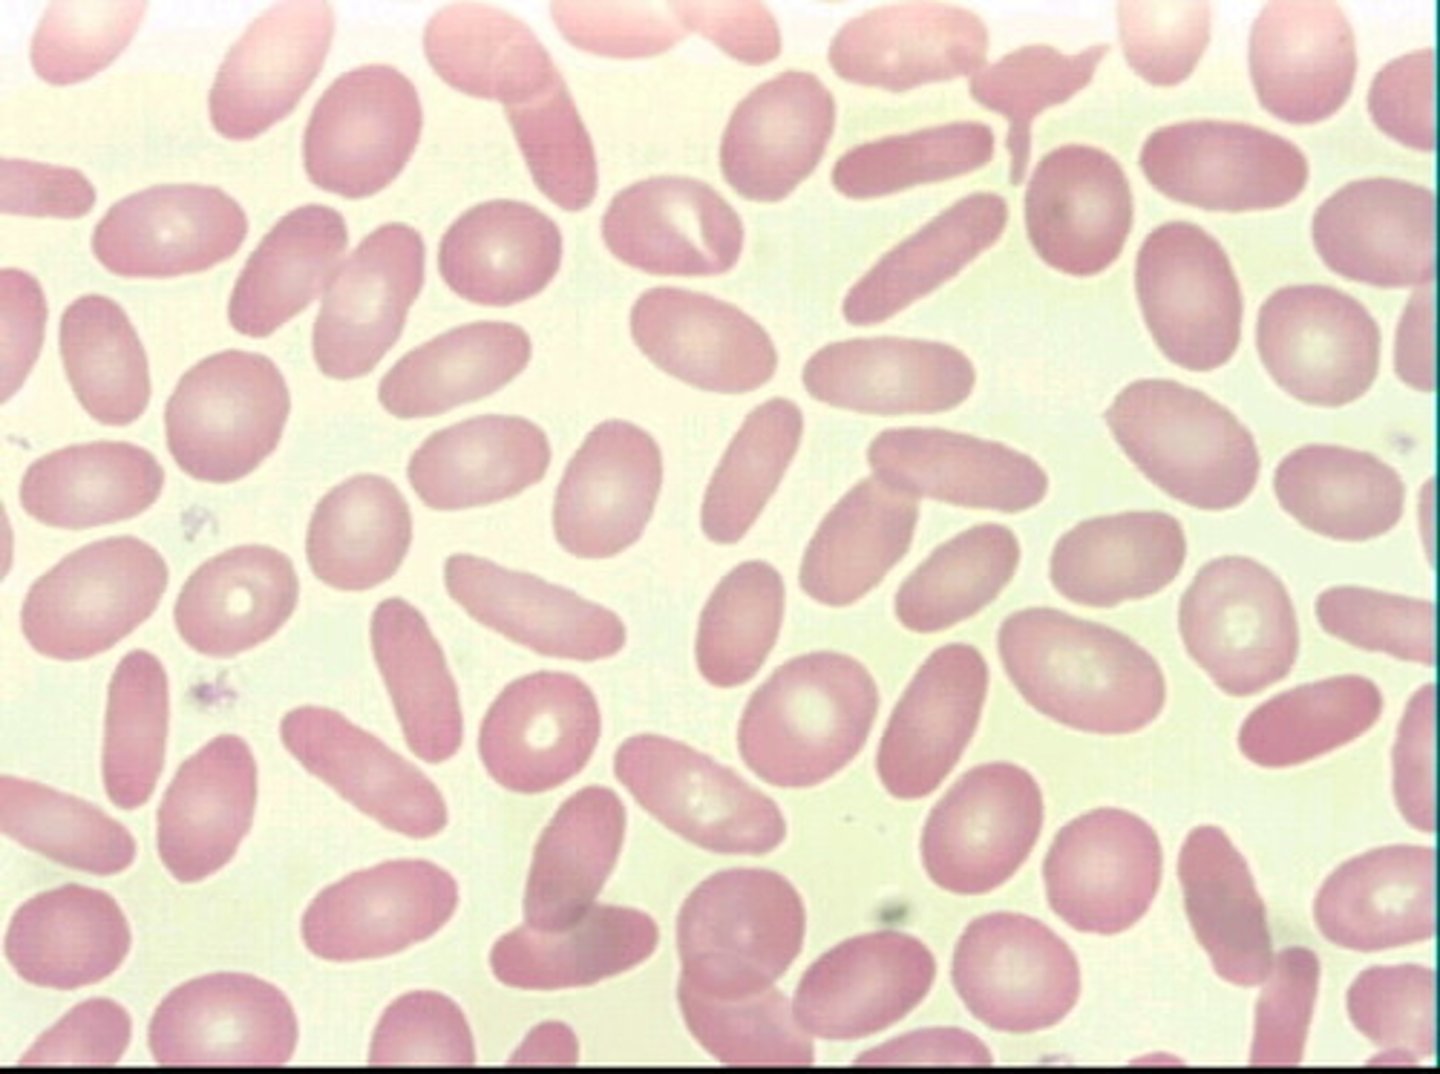

sickle shaped RBC AKA drepanocyte

deer

ovalocytes/elliptocytes

oval in shape